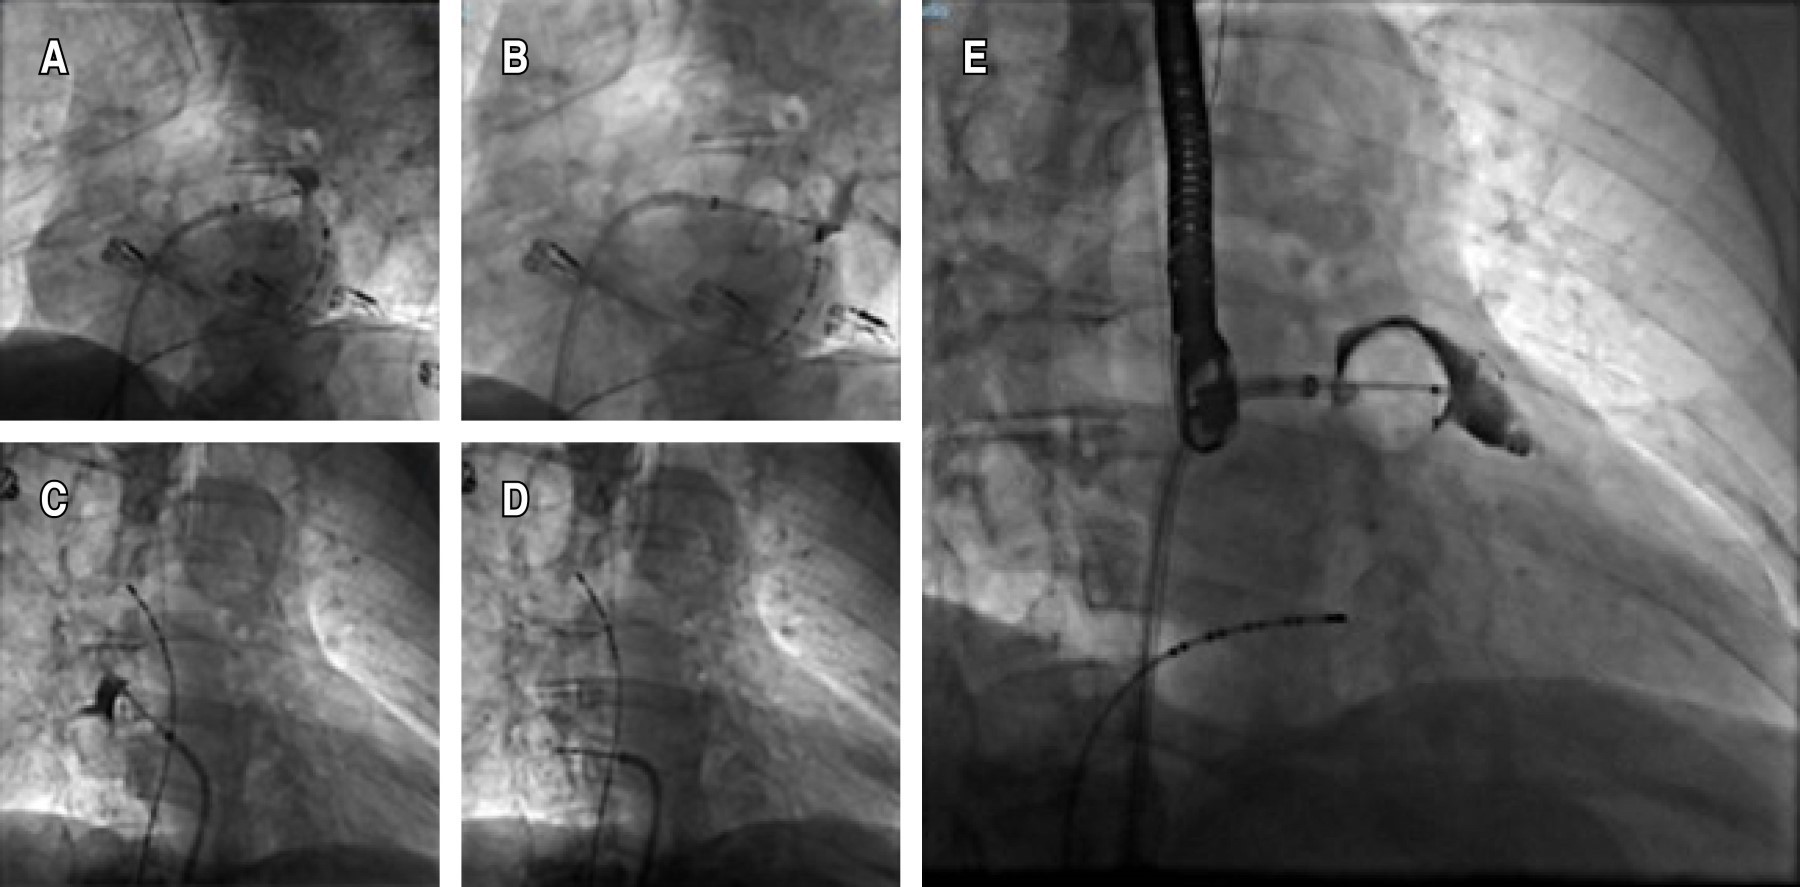

Figura 2

Introducción: al momento de elegir el tratamiento de la fibrilación auricular, es necesario entender al paciente más allá de las puntuaciones de riesgo, comprender la necesidad de llevar a ritmo sinusal o a metas de tratamiento y la rapidez que debe emplearse dado el riesgo que confieran sus enfermedades crónicas y los retos que plantean estas enfermedades a las estrategias convencionales. Presentación de caso: masculino de 69 años, con antecedente de colitis ulcerativa crónica inespecífica (CUCI), intervenido con colectomía subtotal, desde entonces con rectorragia abundante, intermitente. En valoración preoperatoria de hernia paraestomal se descubre FA. Con aumento de rectorragia tras inicio de anticoagulación, abundante en cantidad, llegando a requerir hospitalización. Por el estado de hipercoagulabilidad e inmuno-tromboinflamación asociada a CUCI, se consideró prioritario revertir a ritmo sinusal. Se intenta sin éxito cardioversión farmacológica con amiodarona. Fue considerado candidato para realizar ablación con crioterapia tras cardioversión eléctrica fallida, además de cierre de orejuela izquierda por considerarse no candidato a anticoagulación a largo plazo. Se realiza crioablación de las cuatro venas pulmonares sin lograr retorno a ritmo sinusal, por lo que se amplía ablación hacia pared posterior y orejuela izquierda, con lo que se logra yugular la arritmia exitosamente. Por último, se coloca dispositivo de cierre de orejuela izquierdo. Tras tres meses de tratamiento médico óptimo tras cirugía se retira anticoagulación, a más de un año del procedimiento el paciente se encuentra libre de eventos trombóticos y hemorrágicos. Conclusiones: este caso demuestra la importancia de individualizar el abordaje en la fibrilación auricular. Además, la importancia de la ablación extendida en la fibrilación auricular sin origen en las venas pulmonares, así como el cierre del apéndice auricular como estrategia de tratamiento en pacientes en escenarios complejos no candidatos a anticoagulación.